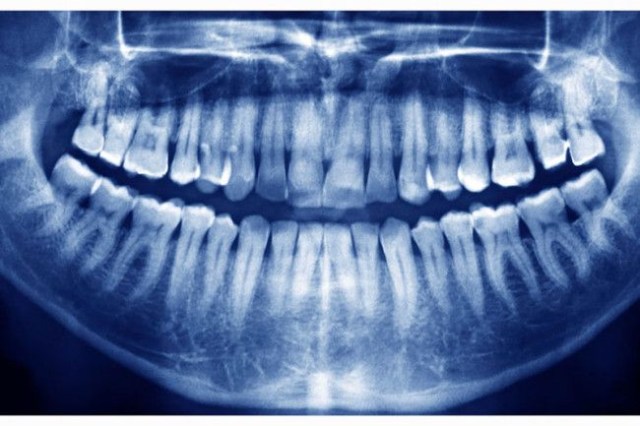

Radiografia panorâmica de uma boca adulta revelando a presença de 28 dentes, indicando a ausência de dentes do siso em desenvolvimento.